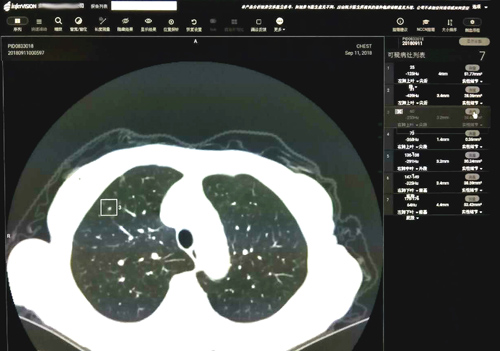

近期,临床医学院/附属医院放射科引进了九江市首套人工智能“InferRead CT Lung”肺部影像诊断辅助软件。该系统融合了大数据与人工智能等最新科技,可以帮助医生大幅度提高肺部结节筛查的效率与准确性。

这款由推想科技提供的软件结合临床医学院/附属医院最先进的 256排512层高端螺旋CT扫描的肺部图像,以其高性能的并行运算能力,通过测量CT值识别出实性、磨玻璃及钙化结节并同时显示所有结节的大小、体积。有了该软件的辅助,再小的结节也不易漏诊。影像科医生对检测的结节进行分析,反馈至软件中标记假阴性的结节和取消假阳性结节的标记。此外,它可通过对影像组学的自我深度学习,提高对图像全信息识别利用的诊断准确性;并且它的知识经验会随着病例增多不断自我优化,从而不断降低漏诊率、误诊率。